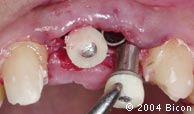

34. | 种植体内径及龈袖口。 |